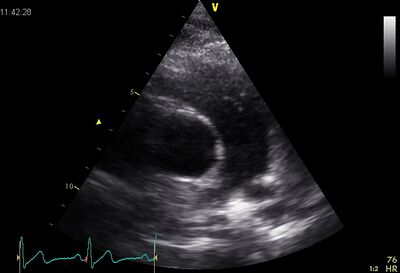

Echocardiographic views

Pulm art02.jpg Pulm art03.jpg

PSAX ao Plax by tilted